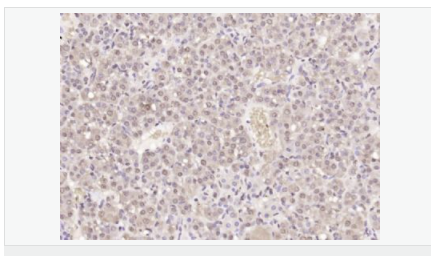

交叉反應(yīng):Human,Mouse,Rat(predicted:Pig,Cow,Rabbit,Sheep) 推薦應(yīng)用:WB,IHC-P,IHC-F,IF,Flow-Cyt,ELISA

| 產(chǎn)品應(yīng)用 | WB=1:500-2000 ELISA=1:5000-10000 IHC-P=1:100-500 IHC-F=1:100-500 Flow-Cyt=1μg/Test ICC=1:100 IF=1:100-500 (石蠟切片需做抗原修復(fù)) not yet tested in other applications. optimal dilutions/concentrations should be determined by the end user. |